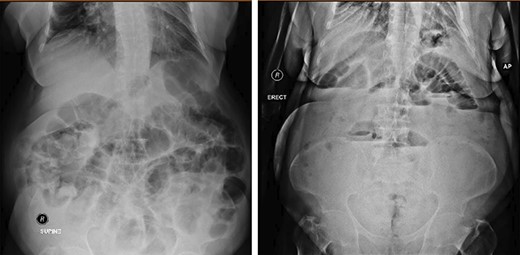

Erect abdominal film demonstrated dilated small bowels alongside the presence of air-fluid filled loops (Fig. 1). Abdominal ultrasound revealed extensively dilated small bowels with multiple gas-filled levels with maximum diameter of 3.5 cm (Fig. 2). Computed tomography (CT) showed the presence of dilated small bowels and local bowel thickening, compatible with the features of small bowel obstruction (Fig. 3). Laboratory data were grossly normal with no evidence of electrolyte abnormalities or increased white blood cell count.

Both supine and erect X-ray show dilatation of the small-bowel.